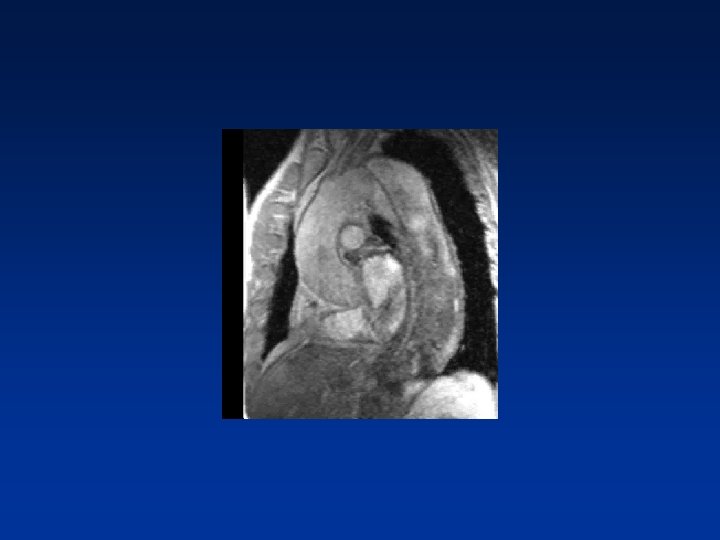

Doenças da aorta torácica • Dissecção aguda da aorta(tipo B) • Dissecção crônica da aorta • Hematoma intramural • Aneurisma verdadeiro • Pseudoaneurisma

Tratamento Endovascular

Endoprótese Torácica E. Saadi/2008

Avaliação Pós-Procedimento Acompanhamento com TC de Múltiplos detectores ou eco TE 30 dias após procedimento e 1 x/ano - Vazamentos(endoleaks) - Expansão do falso lúmen ou aumento do aneurisma - Migração ou falha estrutural da endoprótese